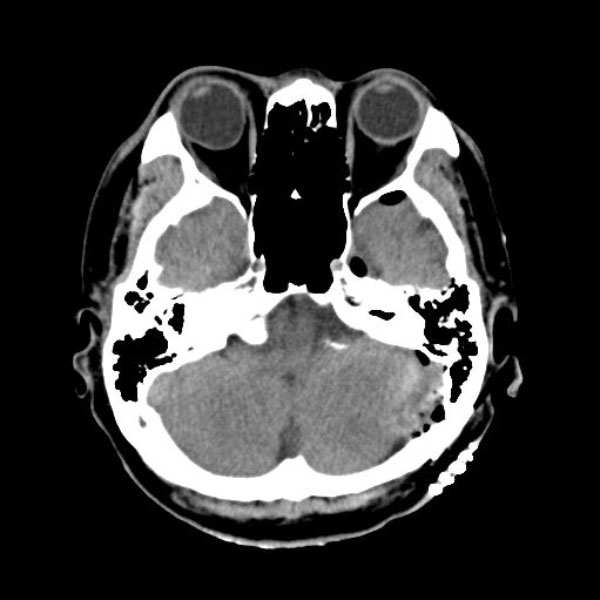

手術後

(CT)